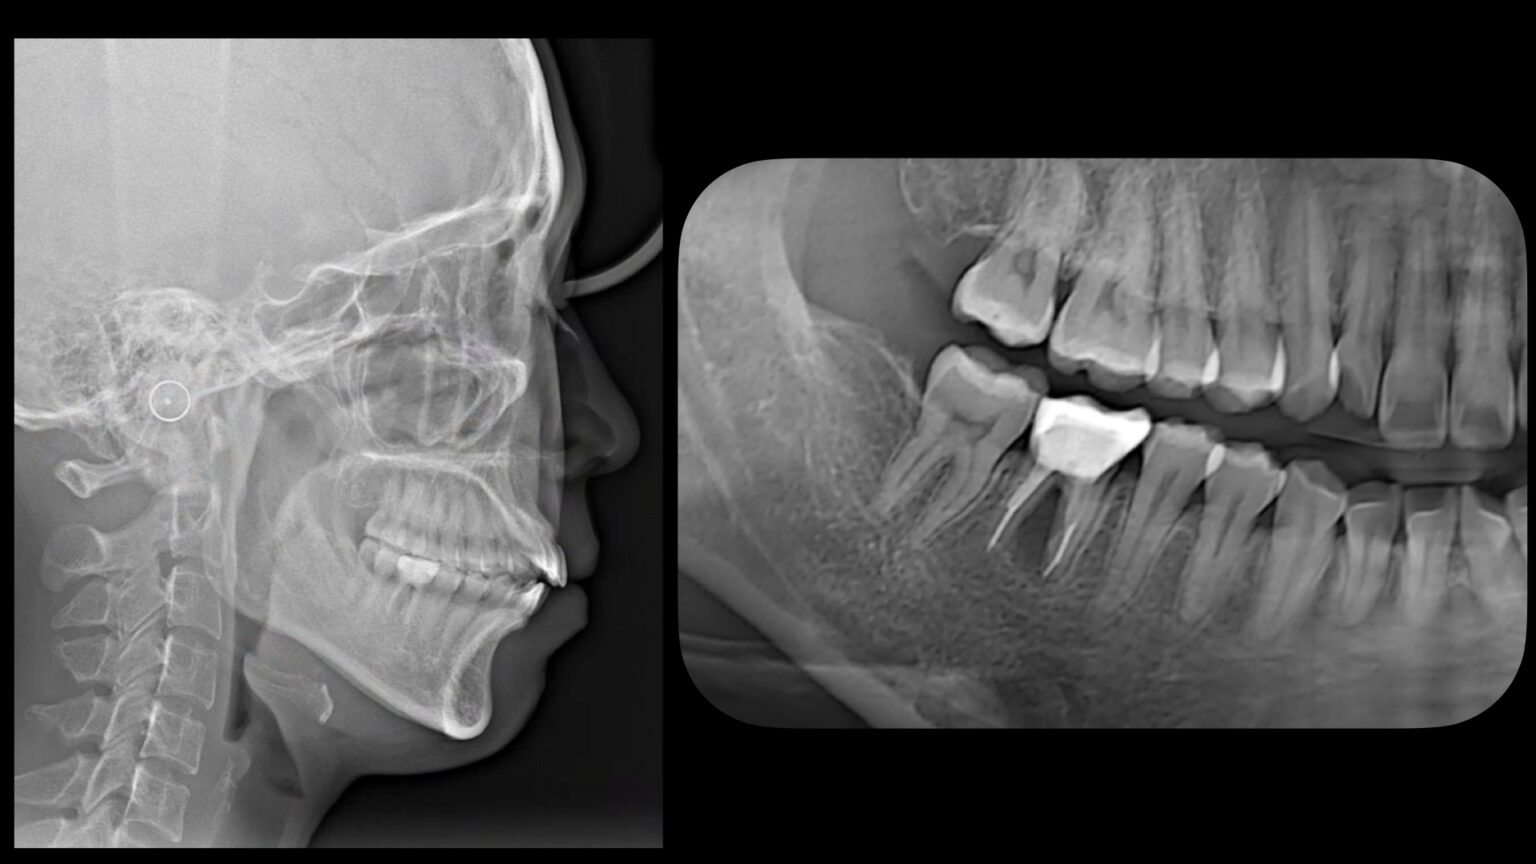

■ 初診時所見

口腔内では以下の問題が認められました。

・上下前歯の叢生(ガタガタ)

・開咬(前歯が咬み合っていない状態)

・下顎右側第一大臼歯の補綴物

顔貌では、口元の突出感を認めました。

また、パノラマX線写真では、

下顎右側第一大臼歯の分岐部に透過像を認め、歯根破折が疑われ、保存不可能と判断しました。

セファロ分析では、上下前歯の前方傾斜が認められました。